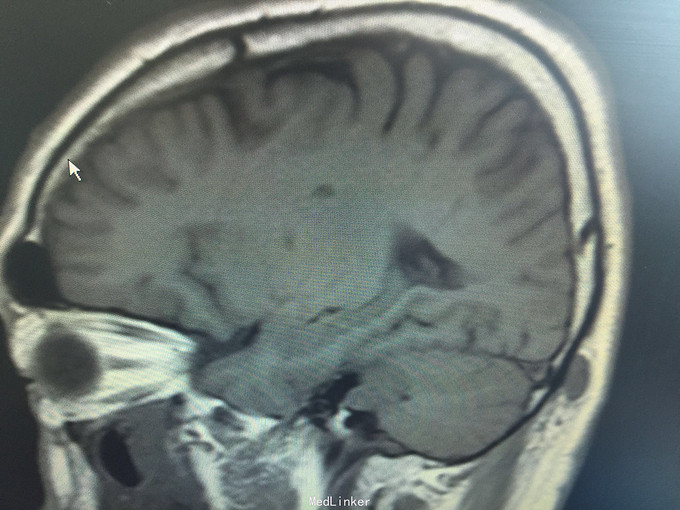

男,52岁,以“左耳鸣、听力下降1年余”入院。 现病史:1年余前看电视时出现左耳鸣、听力下降,左耳听电视声音时听不清,较右侧明显下降,未在意,之后听力下降逐渐至丧失! 既往史:既往高血压、糖尿病病史,长期吸烟病史。 家族史:无特殊!

查体:BP:150/90mmHg,心肺腹未见异常,神清语明,左耳听力丧失,无面瘫,双瞳孔等大正圆,直径约3.0mm,光敏,四肢肌力5级,肌张力正常,巴氏征R-L-。

1.左侧听神经瘤